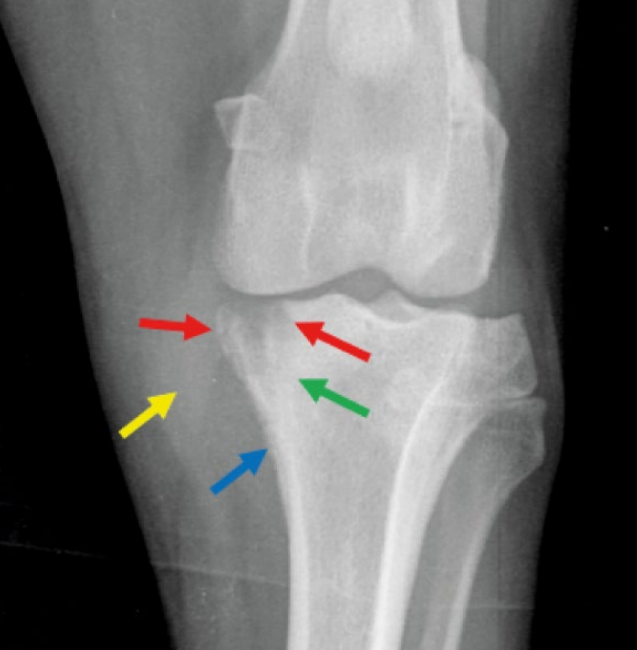

- 관절 양측에서 뼈의 변화가 나타남 - subchondral bone & cortex의 lysis, new bone production

![]() | - 뚜렷하게 나타나기 시작한 부위. 흐릿하게 퍼져 있는 부분. |

![]() | - density도 떨어져 있음 |